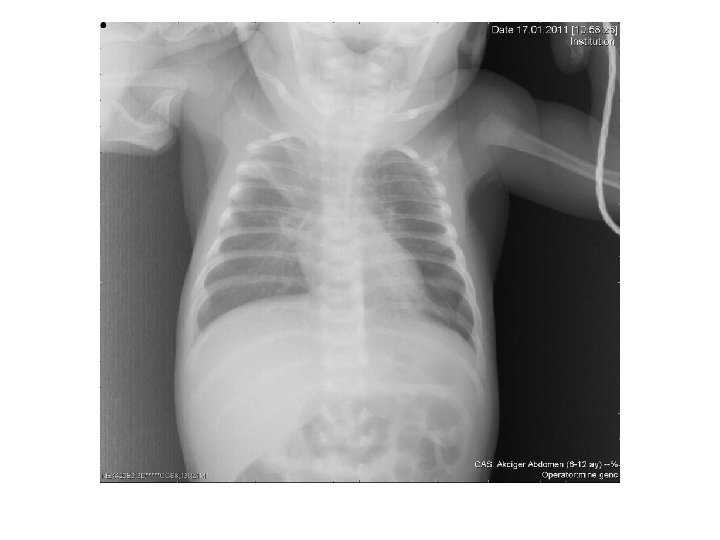

Radyoloji – Havalanma artışı (%35) • Diyaframda düzleşme • Kostalarda düzleşme • Göğüs ön-arka çapında artma – – Peribronşial kalınlaşma (%30) Fokal atelektazi (%15) Hava hapsi alanları (%5) Normal (%38. 7) Fitzgerald DA, Kilham HA. MJA 2004; 180: 399 -404.